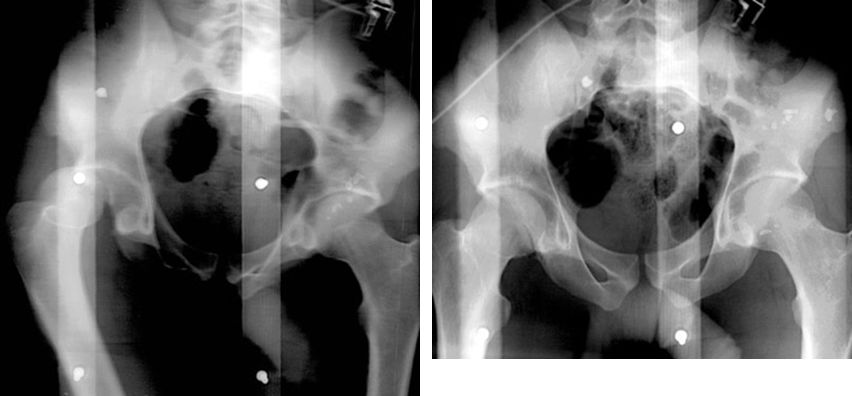

髋关节后脱位

髋关节前脱位

先天性髋脱位

常见髋关节测定线

骨盆骨折